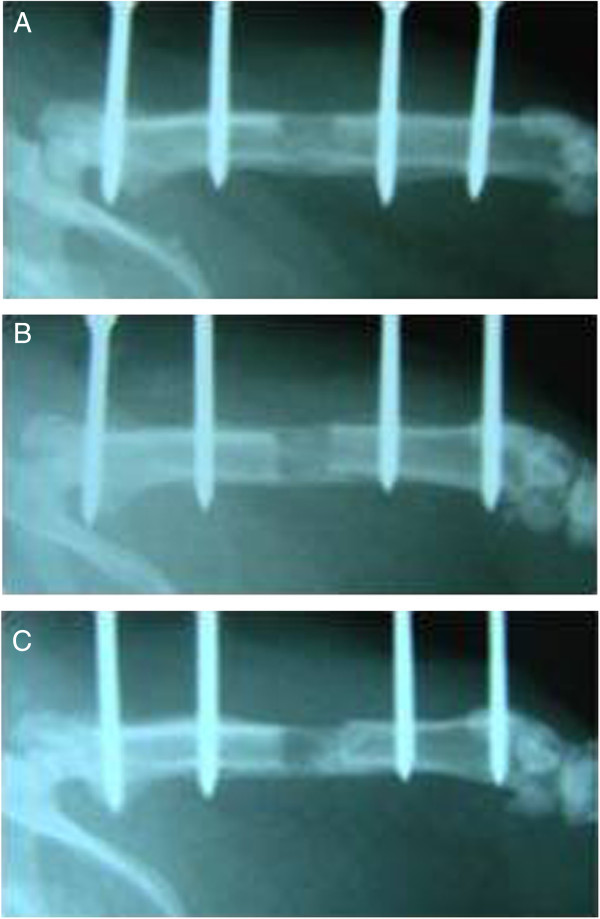

The study was completed with 33 rats due to the death of two rats in group 1, two in group II, and two in group III due to unexpected death, infection, and diarrhea. Histological and radiological results obtained at the end of 82.days were not statistically significant, but we observed better regeneration in groups 1 and 2 compared with group 3. The mean radiological score for group 1 was 9.18 ± 0.6, 9.09 ± 0.54 for group 2, and 8.64 ± 0.5 for the control group (Figure 3A-C). The mean histological score for group 1 was 9.09 ± 0.3, 9.0 ± 0.44 for group 2, and 8.82 ± 0.4 for the control group. During the histopathological examination, significant osteoblastic activity in the distraction area, trabecular bone formation were observed. Trabecular bone tissue was the dominant component in callus tissue of the group 1 and 2, whereas cartilaginous tissue was apparent in group 3. And also we detected significant osteoblastic activity and apparent callus formation in group 1 and 2 compared to group 3. There is not a statistically significant results among the groups (p > 0.05) (Table 3) (Figure 4A-C).

Figure 3.

The radiographic evaluation of the femurs at the end of 82 days. A: The regeneration of the distraction part consisted of bone formation, proximal and distal union, and remodeling. The maximal total score was 10. B: CAPE group: The regeneration of the distraction part showed bone formation, proximal and distal union, and remodelling at the end of 82 days. The maximal total score was 10. C: Control group: The regeneration of the distraction part showed bone formation, proximal and distal union, but limited remodeling. The maximal total score was 9.